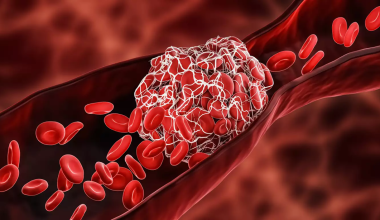

Αν και μερικοί εξισώνουν τους όγκους του εγκεφάλου με τον καρκίνο, μόνο περίπου το ένα τρίτο των όγκων του εγκεφάλου είναι καρκινικοί. Αλλά είτε είναι καρκινικοί είτε όχι, οι όγκοι μπορούν να επηρεάσουν την λειτουργία του εγκεφάλου και την υγεία σας, εάν γίνουν αρκετά μεγάλοι ώστε να πιέζουν τα γύρω νεύρα, τα αιμοφόρα αγγεία και τους ιστούς.